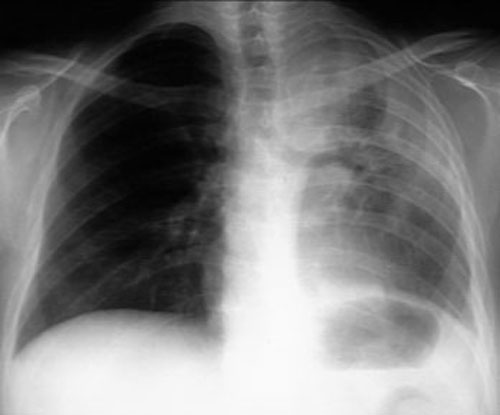

Left upper lobe atelectasis from endobronchial metastasis

from cancer cervix. |

- The usual roentgen findings are bronchial obstruction and

obstructive atelectasis or pneumonia.